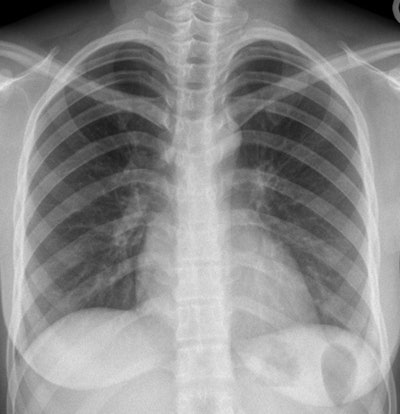

This CXR of a 26-year-old female Afghani refugee was normal at screening, but she was later diagnosed with pulmonary TB. Image courtesy of Dr. Julius Weinrich.TB is a leading cause of death worldwide, and migrants are generally considered to be a high-risk group for carrying it. By law in Germany, all nonpregnant female and all male immigrants older than 15 and to be admitted to shared accommodation sites are obliged to undergo TB screening by CXR.